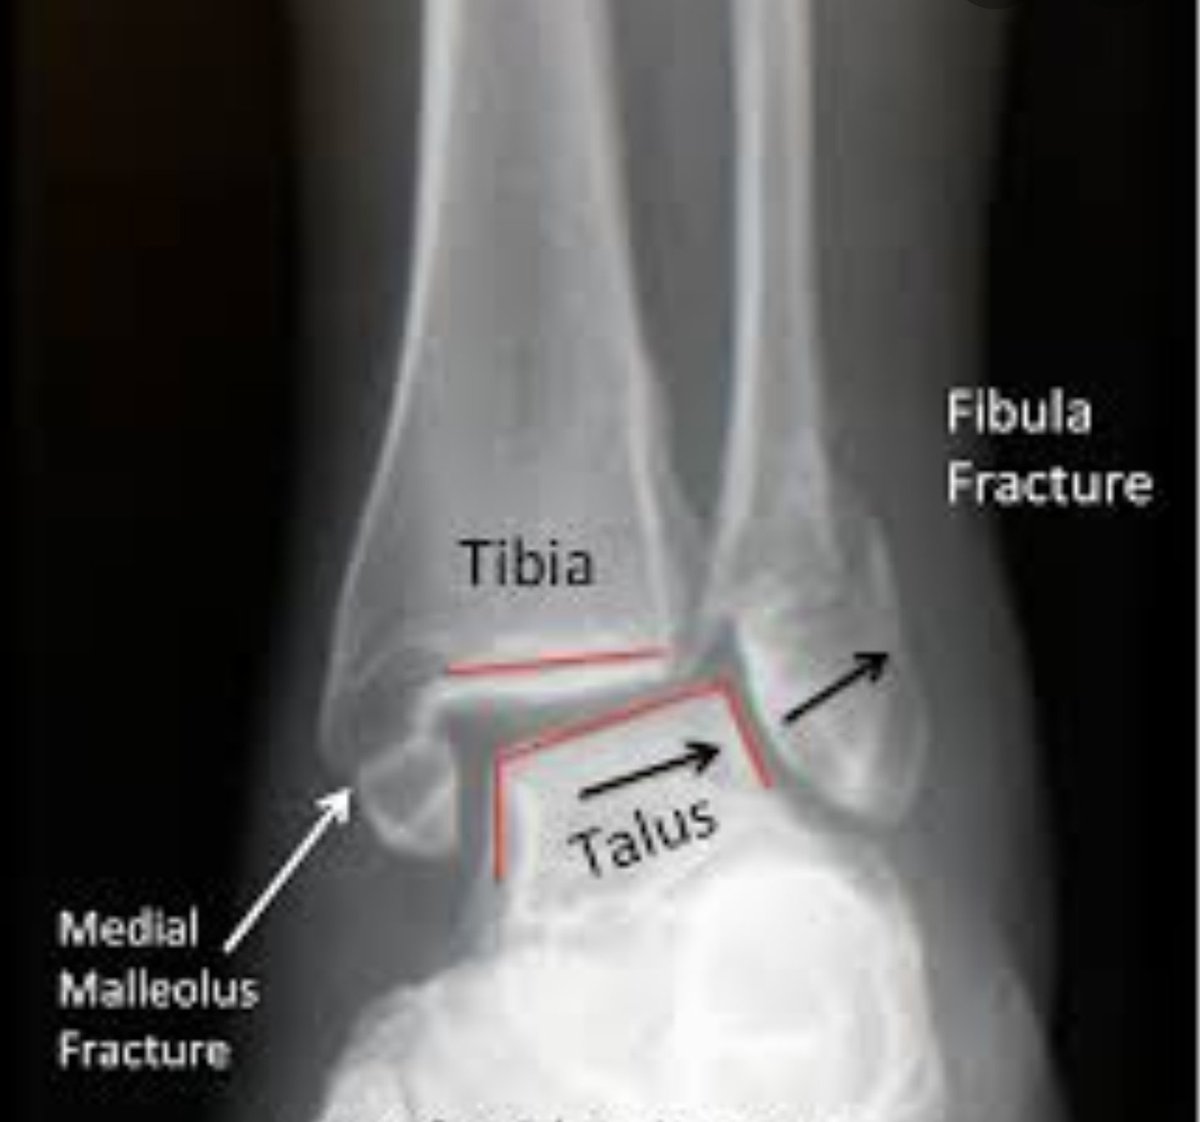

الأشعة:

التشخيص يكون عن طريق أشعة الرنين المغناطيسي

كسور القدم والكاحل